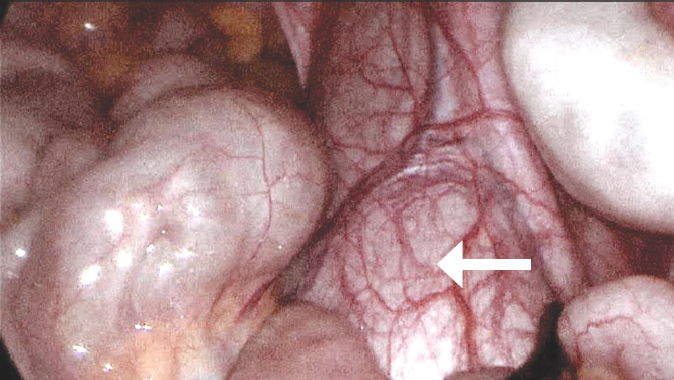

Fig. 3. Type of detected retroperitoneal cystic formation (indicated by a black arrow), along the anterior wall of which the right ureter is visualized (indicated by an arrow with a contour)

Рис. 3. Вид обнаруженного забрюшинного кистозного образования (черная стрелка), по передней стенке которого визуализируется правый мочеточник (белая стрелка)

The patient was admitted to the operating room with a diagnosis of cystic pelvic lesion. Laparoscopic isolation of the mass with the pelvic part up to 10 × 7 × 5 cm showed that it ended blindly at the level of the round ligament of the uterus (Fig. 2–4). As the cystic mass was isolated more proximally, its tight attachment to the right ureter, stenosis, and extension towards the kidney were noted. The right kidney and its hilum were accessed, and the cystic lesion was found to be an atretic, highly dilated ureter of the lower segment of the duplex right kidney (Fig. 5). Its inferior segment was hypoplastic, measuring up to 12 × 10 × 10 mm, with virtually no parenchyma. Therefore, it was decided to perform an inferior heminephroureterectomy. The final view and schematic presentation of the extracted mass are shown in Figure 6 and Figure 7, respectively. The postoperative course was uneventful. The patient had no active urinary tract infections. Laboratory parameters of renal metabolism were normal, and early postoperative ultrasound showed no abnormalities in the remaining right upper kidney.